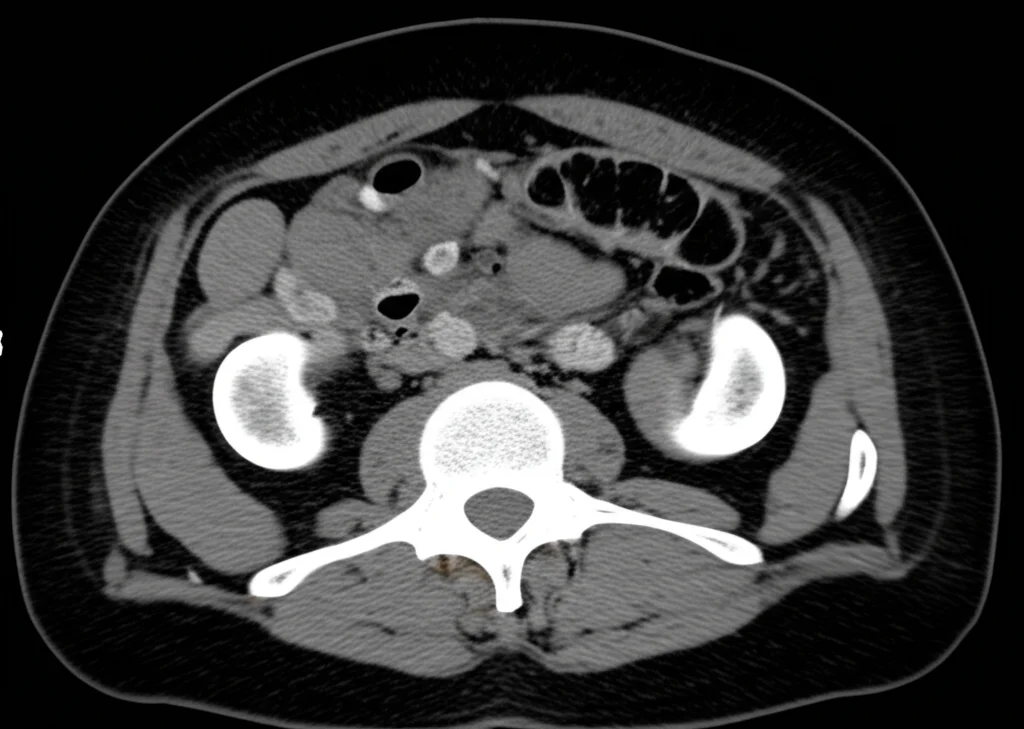

L’obiettivo era chiaro: valutare se il punteggio ALBI-Sarcopenia potesse prevedere l’efficacia dei diversi trattamenti somministrati secondo le linee guida BCLC (Barcelona Clinic Liver Cancer). Abbiamo raccolto dati clinici, di laboratorio, valutato la sarcopenia tramite imaging (TC o RMN a livello della terza vertebra lombare, L3) e calcolato i punteggi ALBI, MELD (Model for End-Stage Liver Disease) e, ovviamente, ALBI-Sarcopenia. Abbiamo poi monitorato la risposta ai trattamenti (completa, parziale, malattia stabile o progressiva) a intervalli regolari.